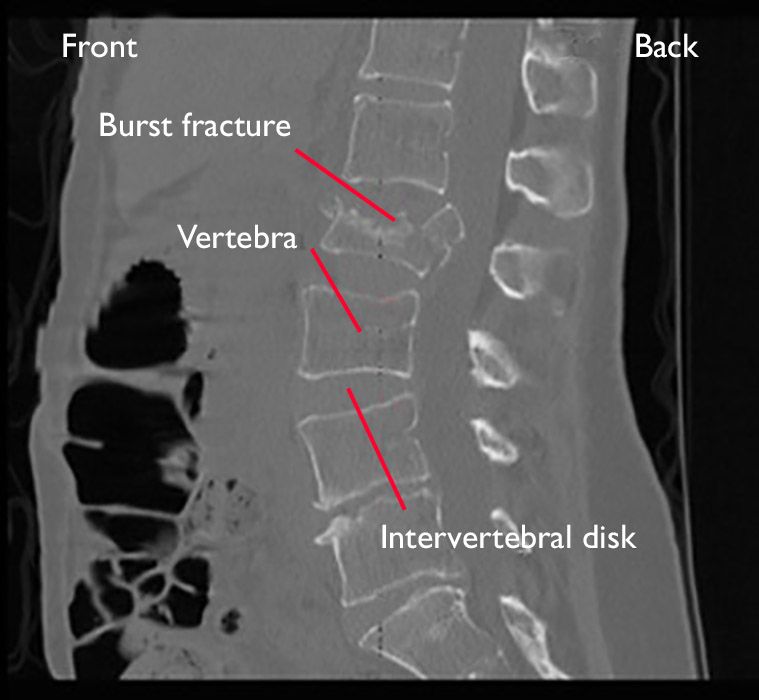

Burst fracture.  In a burst fracture, both the front and the back of the vertebra are broken. Burst fractures can be caused by landing on the feet after falling from a significant height.

This type of fracture:

• Can sometimes result in nerve compression

• Is sometimes stable and sometimes unstable (the spine is not able to support the weight of your body without causing the bones to shift or move)

• May require surgery, depending on the stability of the spine and whether there is nerve injury

CT scan of a burst fracture in the lumbar spine

A CT scan taken from the side of a burst fracture in the lumbar spine.